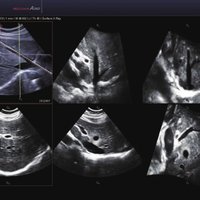

Das Samsung Accuvix A30 ist ein hochwertiges Ultraschallsystem, das mit seiner 3D-Technologie herausragende Ergebnisse ermöglicht. Das Sonographiegerät besitzt 5 Sondenanschlüsse und ist mit 20 unterschiedlichen Schallköpfen kompatibel. Mit dem A30 können Schallköpfe vom Typ Konvex, Mikrokonvex, 3D-Konvex, CW, Phased Array, Linear und Endokavitär verwendet werden. Bei zwei der Sonden handelt es sich um S-VUE Ultraschallsonden, die durch ihre höhere Bandbreite noch feinere Scans erzeugen.

Das Ultraschallsystem hebt sich besonders durch seine 3D-Technologie wie die Face Auto Detection für detaillierte Ultraschallbilder von Föten oder das Volume Shade Imaging, das sich auf die lebensnahe Darstellung von Schattierungen und Hauttönen fokussiert, ab. Mit weiteren wertvollen Technologien wie dem ElastoScan™ werden Tumore schneller erfasst und durch die HD Volumen Bildgebung sowie das DMR+™ eine erstklassige Bildqualität erzielt.

• FAD™, die Face Auto Detection, stellt das Gesicht eines Fötus besonders detailliert dar. Überflüssige Daten werden entfernt und ein besonders realistisches Bild gezeichnet.

• Volume Shade Imaging, kurz VSI™, visualisiert ein 3D-Bild, das Hauttöne und Schattierungen auf ein qualitativ neues Niveau hebt.

• Die HD Volumen Bildgebung reduziert unerwünschte Streumuster und sorgt für eine präzisere Darstellung der Bilder.